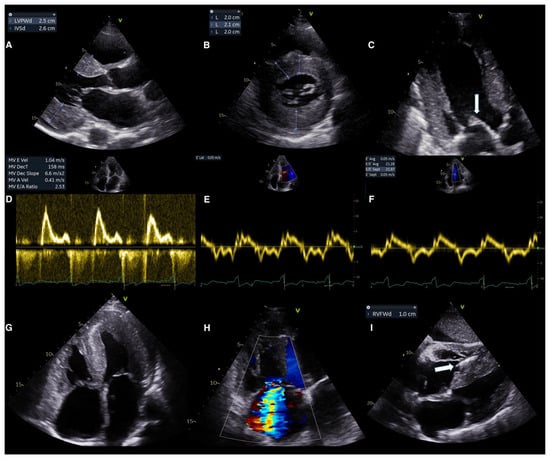

6.1. Echocardiography for Diagnosis

Conventional Echocardiography

6.2. Advanced Echocardiography

- Cuddy, S.A.M.; Chetrit, M.; Jankowski, M.; Desai, M.; Falk, R.H.; Weiner, R.B.; Klein, A.L.; Phelan, D.; Grogan, M. Practical Points for Echocardiography in Cardiac Amyloidosis. J. Am. Soc. Echocardiogr. 2022, 35, A31–A40. [Google Scholar] [CrossRef]

- Polo, J.M.; Barrenechea, A.R.U.; Martí, P.R.; Palacios, R.P.; Gutiérrez, A.G.; Juana, E.B.; Gracia, A.A.; Ayala, S.A.; Arregui, M.Á.A. Echocardiographic Markers of Cardiac Amyloidosis in Patients with Heart Failure and Left Ventricular Hypertrophy. Cardiol. J. 2023, 30, 266–275. [Google Scholar] [CrossRef]

- Licordari, R.; Minutoli, F.; Recupero, A.; Campisi, M.; Donato, R.; Mazzeo, A.; Dattilo, G.; Baldari, S.; Vita, G.; Zito, C.; et al. Early Impairment of Right Ventricular Morphology and Function in Transthyretin-Related Cardiac Amyloidosis. J. Cardiovasc. Echogr. 2021, 31, 17–22. [Google Scholar] [CrossRef]

- Bodez, D.; Ternacle, J.; Guellich, A.; Galat, A.; Lim, P.; Radu, C.; Guendouz, S.; Bergoend, E.; Couetil, J.P.; Hittinger, L.; et al. Prognostic Value of Right Ventricular Systolic Function in Cardiac Amyloidosis. Amyloid 2016, 23, 158–167. [Google Scholar] [CrossRef]

- Chacko, L.; Karia, N.; Venneri, L.; Bandera, F.; Passo, B.D.; Buonamici, L.; Lazari, J.; Ioannou, A.; Porcari, A.; Patel, R.; et al. Progression of Echocardiographic Parameters and Prognosis in Transthyretin Cardiac Amyloidosis. Eur. J. Heart Fail. 2022, 24, 1700–1712. [Google Scholar] [CrossRef]

- Garcia-Pavia, P.; Bengel, F.; Brito, D.; Damy, T.; Duca, F.; Dorbala, S.; Nativi-Nicolau, J.; Obici, L.; Rapezzi, C.; Sekijima, Y.; et al. Expert Consensus on the Monitoring of Transthyretin Amyloid Cardiomyopathy. Eur. J. Heart Fail. 2021, 23, 895–905. [Google Scholar] [CrossRef]

- Shah, S.J.; Fine, N.; Garcia-Pavia, P.; Klein, A.L.; Fernandes, F.; Weissman, N.J.; Maurer, M.S.; Boman, K.; Gundapaneni, B.; Sultan, M.B.; et al. Effect of Tafamidis on Cardiac Function in Patients with Transthyretin Amyloid Cardiomyopathy: A Post Hoc Analysis of the ATTR-ACT Randomized Clinical Trial. JAMA Cardiol. 2024, 9, 25–34. [Google Scholar] [CrossRef]

- Ichikawa, Y.; Oota, E.; Odajima, S.; Kintsu, M.; Todo, S.; Takeuchi, K.; Yamauchi, Y.; Shiraki, H.; Yamashita, K.; Fukuda, T.; et al. Impact of Tafamidis on Echocardiographic Cardiac Function of Patients with Transthyretin Cardiac Amyloidosis. Circ. J. 2023, 87, 508–516. [Google Scholar] [CrossRef]